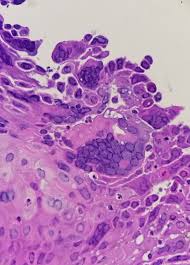

Herpes simplex virus multiple superficial ulcers are common (details from endoscopy) biopsy edge of ulcer — intranuclear inclusions found in squamous mucosa can see detached squamous cells as well as macrophages with viral incusions in ulcer slough inclusions are usually obvious Herpes esophagitis, however, is usually an opportunistic infection but can also occur in immunocompetent. The key feature is acantholysis with solitary keratinocytes within the blister cavity (figures 1,2,3). Ulcers can coalese and form black esophagus histology will show eosinophilic intranuclear inclusions (cowdry type a) and multinucleated squamous cells surrounding the ulcers on biopsy; It can be a consequence of viremia, reactivation of hsv, or even a direct spread of the virus to esophageal mucosa from the vagus nerve in immunocompromised patients. Herpes esophagitis is an inflammation of the esophagus due to herpes simplex virus. Herpetic esophagitis (eh) caused by herpes simplex virus (hsv) usually affects immunocompromised patients, as a primary infection or as a reactivation of a previous infection. Herpes esophagitis is a viral infection of the esophagus.

#2 most common cause of infectious esophagitis after candida self limited in healthy patients; Abstract herpes simplex virus (hsv) is a common cause of infectious esophagitis. Esophagitis caused by herpes simplex virus (hsv) is frequently documented during periods of immunosuppression in patients infected with human immunodeficiency virus (hiv). Ultimate gut formula that heals your esophagus naturally with 4 powerful nutrients. It can occur in immunocompromised patients as well as healthy individuals over a wide age range, including children and young adults. Know the real cause of esophagitis & how to heal your digestive system naturally. The key feature is acantholysis with solitary keratinocytes within the blister cavity (figures 1,2,3). The ulcer base at the left shows loss of overlying squamous epithelium with only necrotic debris remaining. Human papillomavirus is detectable in barrett's esophagus and esophageal carcinoma but is unlikely to be of any etiologic significance.. J clin virol 50 (3): Following these findings, the patient received intravenous acyclovir. Herpes simplex virus multiple superficial ulcers are common (details from endoscopy) biopsy edge of ulcer — intranuclear inclusions found in squamous mucosa can see detached squamous cells as well as macrophages with viral incusions in ulcer slough inclusions are usually obvious Can perform cmv immunostain if no classic viral cytopathic effect seen on h&e.

Yellow arrows point to possible viral inclusions. Herpes esophagitis is a viral infection of the esophagus. The key feature is acantholysis with solitary keratinocytes within the blister cavity (figures 1,2,3). Herpetic esophagitis (eh) caused by herpes simplex virus (hsv) usually affects immunocompromised patients, as a primary infection or as a reactivation of a previous infection. It typically occurs in during the third trimester of pregnancy or in immunocompromised patients.